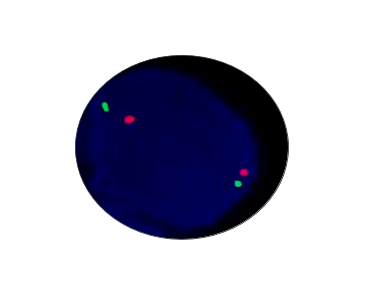

E2A/PBX1 Positive

Probe Description: E2A/PBX1

Cat.No.: CF1254